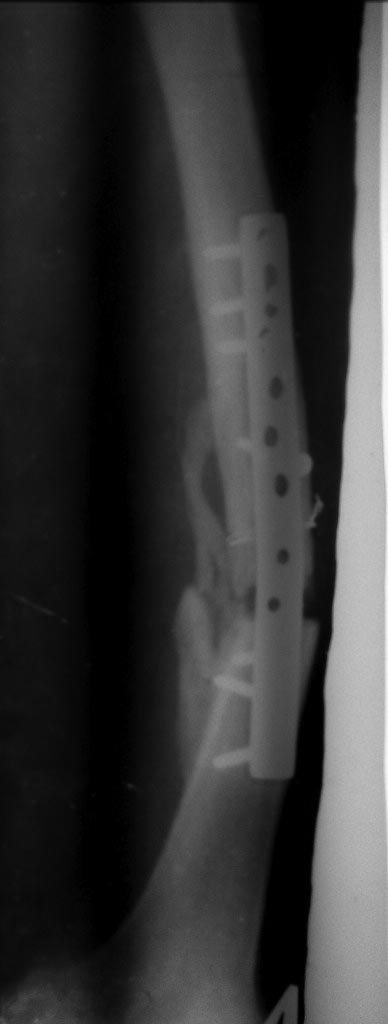

Уважаемые коллеги! Помогите определиться с тактикой лечения у молодого

пациента.

Молодой парень, 25лет. Травму получил в ноябре 2012 года, ДТП.Оперирован

в сельской больнице, остеосинтез перелома бедренной кости пластиной и

АВФ на голень с этой стороны, наложена гипсовая повязка коксит на 3

месяца. В момент госпитализации разгибательная контрактура коленного

сустава (движения в коленном суставе сгибание 10 градусов) 02.07.2013

рентгенапаратом. Как быть с ложным суставом голени?

1. БИОС голени- оптимальный вариант,но при отсутствии желаемого сгибания

в коленном суставе сможем ли мы сделать( Наш опыт - всего 30 операций по

БИОСу)

2ЧКДО по Илизарову( после АВФ)